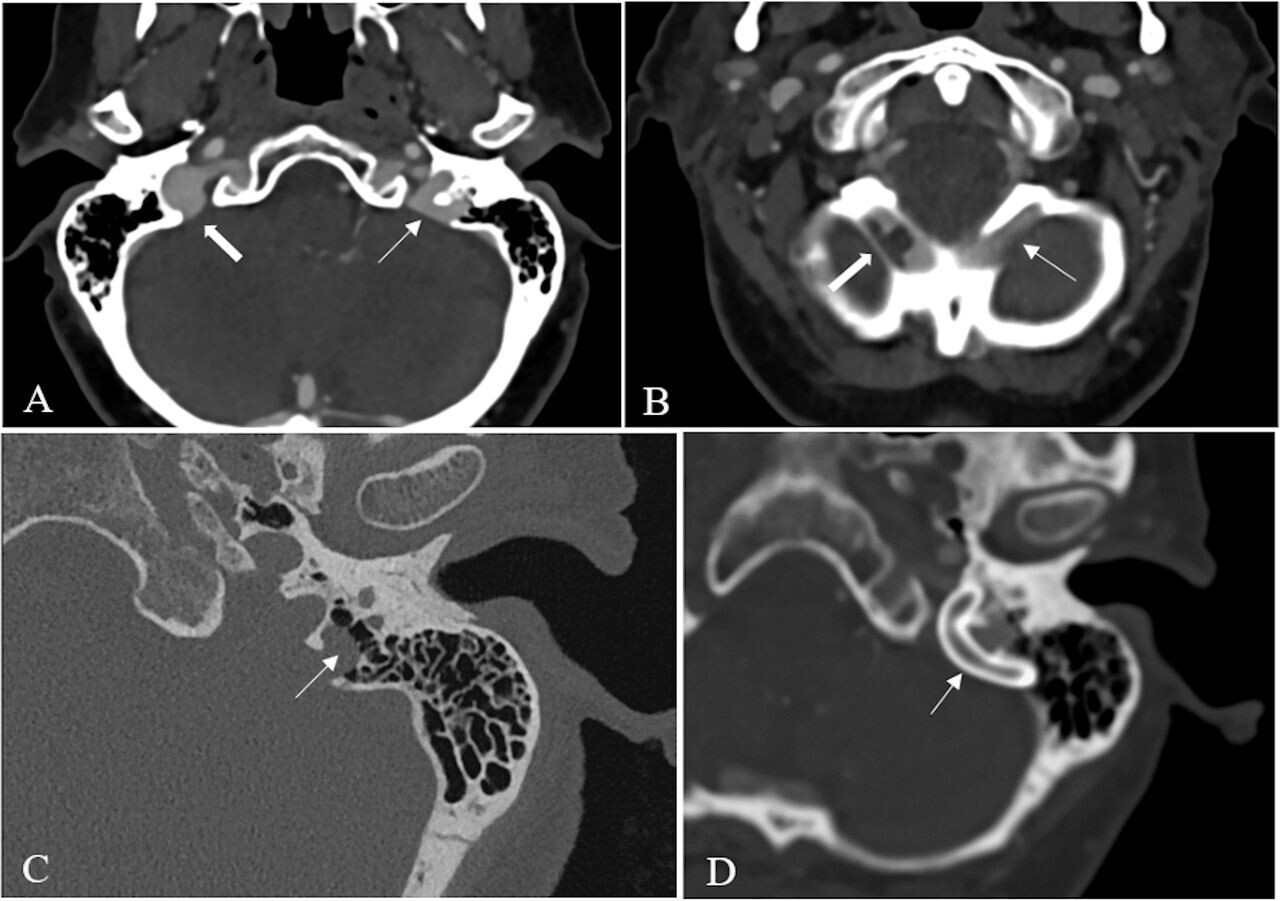

Contexte : Cette étude examine une cause rare d'acouphènes pulsatiles liés à une duplication déhiscente du bulbe jugulaire associée à un sinus occipital oblique dominant non sténosé. Nous rapportons une série de patients traités et décrivons une nouvelle caractéristique radiologique : le « signe du cœur en carte à jouer ».

Résultats : L'âge moyen des patients était de 41,9 ans, avec un indice de masse corporelle médian de 27,4 kg/m². Les acouphènes étaient unilatéraux chez trois patients et alternants chez un. L'imagerie a révélé une déhiscence osseuse recouvrant un bulbe jugulaire dupliqué, ipsilatéral à un sinus occipital oblique dominant non sténosé, sans gradient de pression veineuse. La pose d'un stent (n = 5) a permis une résolution complète des acouphènes chez tous les patients, avec un suivi médian de 15 mois et aucune complication rapportée.

Conclusions : La duplication du bulbe jugulaire avec déhiscence, associée à un sinus occipital oblique dominant non sténosé, représente une cause méconnue d’acouphènes pulsatiles. Cette affection peut efficacement être traitée par stenting. L’identification du « signe du cœur en carte à jouer » à l’imagerie est essentielle pour un diagnostic et une prise en charge précis.

Cette étude identifie une configuration anatomique distincte — la duplication du bulbe jugulaire avec déhiscence associée à un sinus occipital oblique dominant non sténotique — comme cause d’APV. Elle introduit un nouveau signe radiologique, le « signe du cœur de carte à jouer », et montre que la mise en place ciblée d’un stent veineux permet de résoudre efficacement les symptômes sans complications.